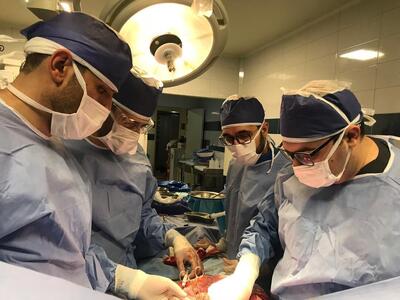

تومور 2کیلویی از بازوی بیمار بابلی خارج شد - تسنیم

عضو هیئت علمی دانشگاه علوم پزشکی بابل از خارج کردن تومور 2کیلویی از بازوی بیمار بابلی در بیمارستان آیت الله روحانی بابل خبر داد.